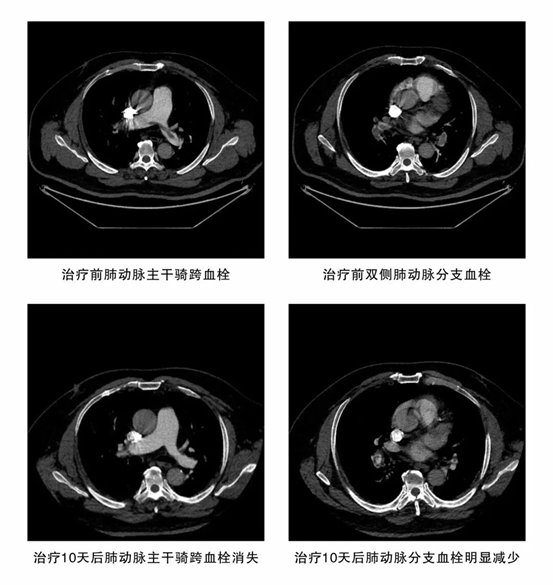

11月1日,一名50多岁的男性患者因“突发心慌、气喘2天”被紧急转入潜江市中心医院。急诊团队迅速识别病情并立即开启绿色通道。检查结果令人震惊:血液D-二聚体飙升至6.61mg/L(远超正常标准),强烈提示血栓形成;肺动脉 CTA 影像更令人揪心——双肺肺动脉从主干到分支布满多发栓塞,最大栓子体积达22.78cm³,右心室已明显扩大。患者病情异常凶险,如同肺部布满“炸弹”,随时可能引爆,造成呼吸循环衰竭,导致猝死。

功夫不负有心人。在医护团队的精心治疗与细心守护下,患者的病情一天天好转。11月11日复查肺动脉CT影像传来捷报,患者肺部血栓已明显吸收;11月19日,患者自觉胸闷、气喘症状已显著缓解。当停用肝素的那一刻,整个医护团队悬着的心终于落下。